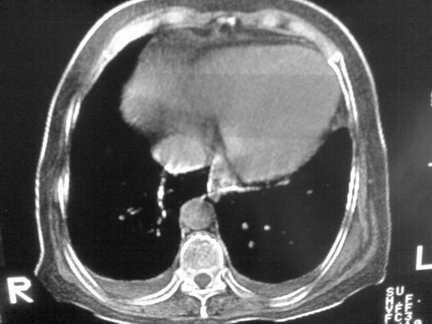

标题: CT13142:女 80 胸闷、气短、1w [打印本页]

标题: CT13142:女 80 胸闷、气短、1w

双侧胸腔积液

胸膜肥厚,

右肺感染;双侧胸腔少量积液,心影增大,可能与心功不全有关;胸内甲状腺肿。

右肺炎性变,双侧甲状腺肿,胸膜肥厚,心影增大考虑心功能不全.

胸内甲状腺肿;右肺中叶感染;双侧胸腔少量积液;心影增大,考虑有心功能不全。